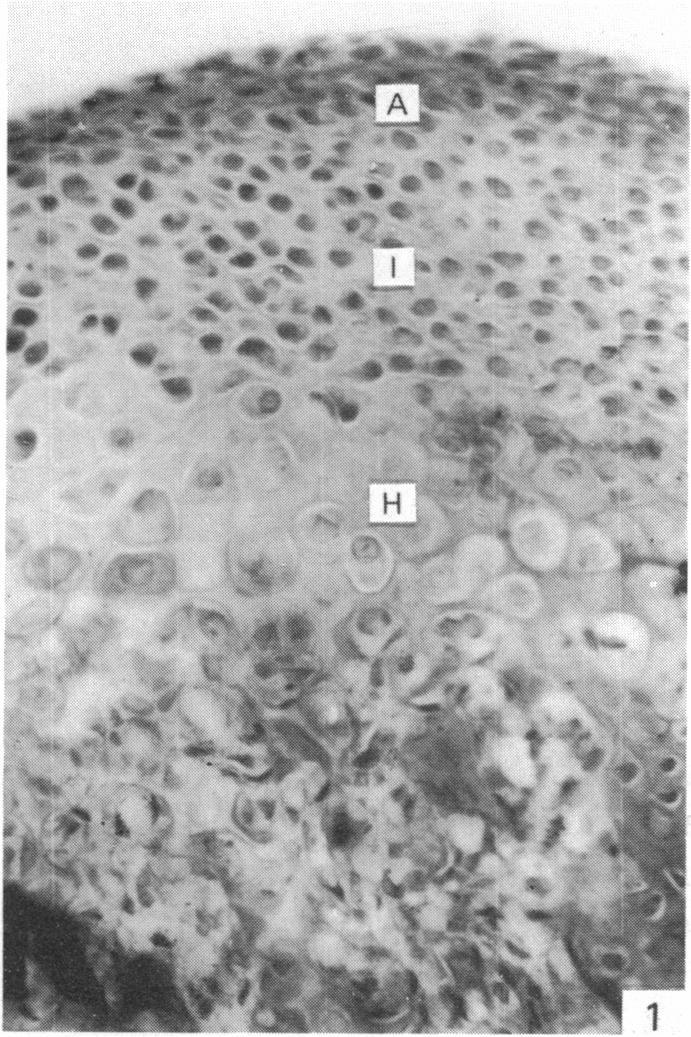

来自矮胖(stm)突变小鼠下颌髁突的异常软骨。

Abnormal cartilage from the mandibular condyle of stumpy (stm) mutant mice.

The mammalian mandibular condyle is composed of secondary cartilage and may thus be susceptible to genes causing achondroplasia and which result in abnormal++ primary cartilage formation. This paper describes the secondary cartilage in the mandible of the stumpy achondroplastic mutation in the mouse: both primary and secondary cartilage are affected by the gene.

哺乳动物的下颌髁由继发性软骨组成,因此可能易受导致软骨发育不全并致使初级软骨形成异常的基因影响。本文描述了小鼠短粗型软骨发育不全突变体下颌骨中的继发性软骨:初级软骨和继发性软骨均受该基因影响。